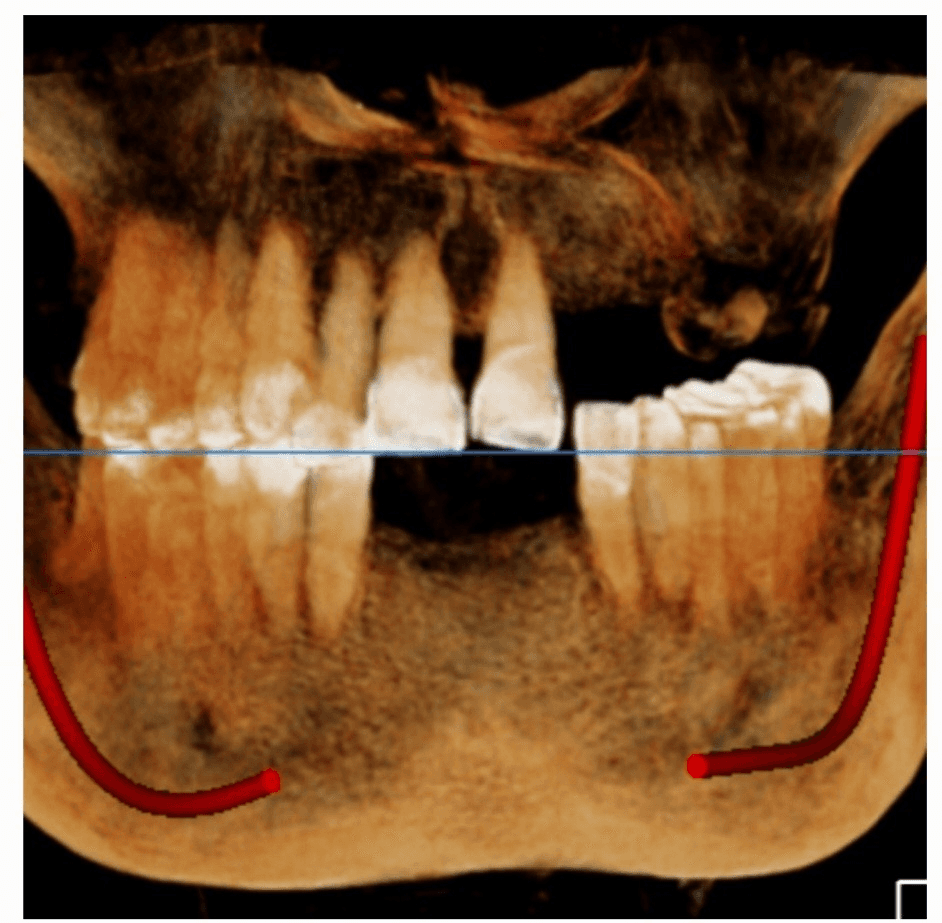

A comprehensive clinical evaluation was performed, followed by a CBCT (Cone Beam Computed Tomography) scan.

The CBCT scan allowed us to carefully assess:

Bone volume and density

Sinus anatomy

Residual ridge height

Critical anatomical landmarks

The findings confirmed severe bone atrophy in the left posterior maxilla, with extremely deficient bone height—making conventional implant placement unsafe.

Post-operative radiographs confirmed:

Excellent graft placement

Proper implant positioning

Successful sinus membrane elevation